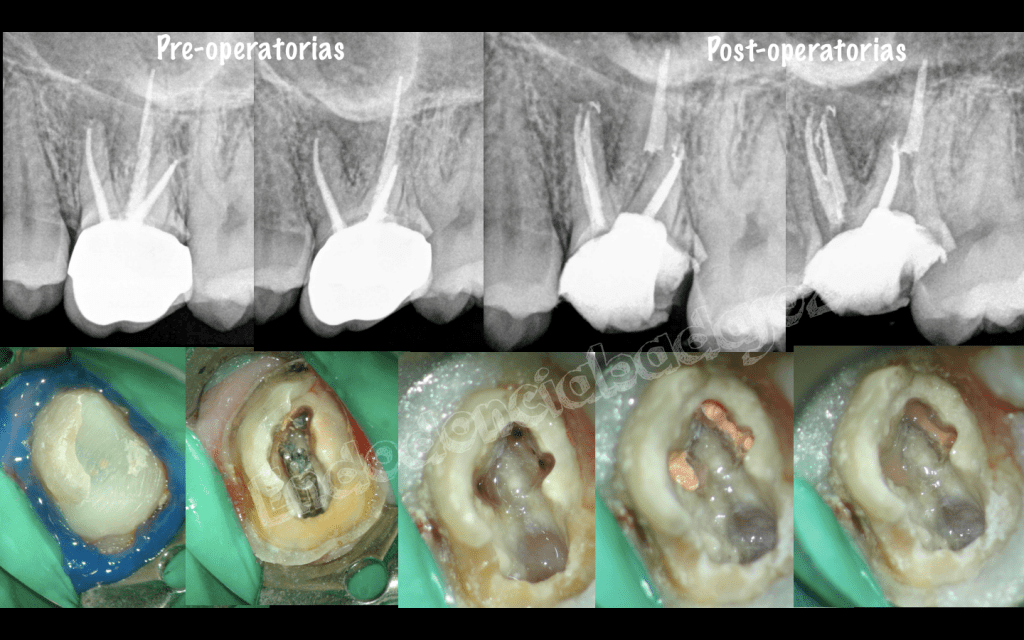

Después de una temporada sin postear ningún caso, hoy me levanté con ganas de publicar alguno, se trata de cinco casos, a mi juicio, interesantes, cuatro endodoncias de molares inferiores con anatomías complicadas y un retratamiento de un molar superior . Espero que os gusten.

• Hola Maru, cada retratamiento es diferente, según la condensación de la gutapercha, utilizo un sistema u otro. Pero generalmente, en este tipo de casos utilizo, las limas Protaper R y limas manuales ( C+ de Maillefer y Hedstrom del 15) hasta permeabilizar. Muchas gracias por tus palabras y espero haberte ayudado.

Aunque todos los casos son muy buenos, el tercero me parece muy bonito. Podría decirme a qué conducto se unía el MM? El preflaring cómo lo hace usted? Usa Gates o utiliza sistemas rotatorios NiTi?